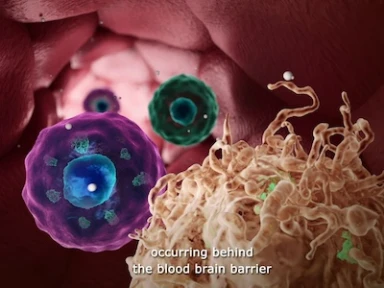

Science in Multiple Sclerosis

Get a global overview and learn all about the changing world of Multiple Sclerosis